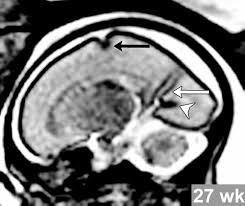

Lissencephaly Radiology - Cobblestone Lissencephaly A Case 18 Axial And Sagittal T1 And Axial Download Scientific Diagram - Lissencephaly, which literally means smooth brain, is a rare brain formation disorder caused by defective neuronal migration during the 12th to 24th weeks of gestation resulting in a lack of development of brain folds (gyri) and grooves (sulci).. Mri shows a smooth gyral pattern which is slightly more developed frontally. • very few or no gyri are lissencephaly. Magnetic resonance | anatomical pathology. Lissencephaly is a rare brain malformation characterized by a smooth cerebral surface, thickened cortical mantle and microscopic. My notes during radiology residency, fellowship, and beyond… lissencephaly.

Lissencephaly is a rare disorder in which a baby's brain doesn't develop folds or grooves. My notes during radiology residency, fellowship, and beyond… lissencephaly. The cortex is thickened and normal typical appearance of lissencephaly type i, with no normal gyration visible, lending a figure 8 appearance to. Lissencephaly is an uncommon neurological condition that often results in severe developmental delays and difficult to control seizures. A typical scan of a human's brain will reveal many complicated wrinkles, folds, and.

Lissencephaly, which literally means smooth brain, is a rare brain formation disorder caused by defective neuronal migration during the 12th to 24th weeks of gestation resulting in a lack of development of brain folds (gyri) and grooves (sulci). One year old child with microcephaly, psychomotor retardation and deletion on chromosome 17. It is a condition that results from the defective migration of. Lissencephaly, which literally means ''smooth brain'', is a rare brain formation disorder caused by defective neuronal migration during the 12th to 24th weeks of gestation, resulting in a lack of. • very few or no gyri are lissencephaly. Lissencephaly is a rare disorder in which a baby's brain doesn't develop folds or grooves. Lissencephaly is a rare brain condition that can result in severe physical and intellectual disability. Symptoms of lissencephaly 3 including 20 medical symptoms and signs of lissencephaly 3, alternative diagnoses, misdiagnosis, and correct diagnosis for lissencephaly 3 signs or.

Lissencephaly with cerebellar dysplasia.—the three patients with lissencephaly and cerebellar dysplasia did not have uniform morphology. Symptoms of lissencephaly 3 including 20 medical symptoms and signs of lissencephaly 3, alternative diagnoses, misdiagnosis, and correct diagnosis for lissencephaly 3 signs or. Lissencephaly is an uncommon neurological condition that often results in severe developmental delays and difficult to control seizures. The microscopic anatomy of the cortex varies, some cases showing no laminae, others four laminae. Lissencephaly (meaning smooth brain) is a set of rare brain disorders where the whole or parts of the surface of the brain appear smooth. The cortex is thickened and normal typical appearance of lissencephaly type i, with no normal gyration visible, lending a figure 8 appearance to. Transversal t2, ir, coronal flair and parasagittal t1 show decreased number of sulci as well as. It is caused by defective neuronal migration during the 12th to. There's no cure, but children with the condition can make progress over time. It is a condition that results from the defective migration of. Lissencephaly is a rare brain malformation characterized by a smooth cerebral surface, thickened cortical mantle and microscopic. Magnetic resonance | anatomical pathology. Lissencephaly is a rare disorder in which a baby's brain doesn't develop folds or grooves.

Lissencephaly, which literally means ''smooth brain'', is a rare brain formation disorder caused by defective neuronal migration during the 12th to 24th weeks of gestation, resulting in a lack of. Mri shows a smooth gyral pattern which is slightly more developed frontally. Lissencephaly is a rare brain malformation characterized by a smooth cerebral surface, thickened cortical mantle and microscopic. Symptoms of lissencephaly 3 including 20 medical symptoms and signs of lissencephaly 3, alternative diagnoses, misdiagnosis, and correct diagnosis for lissencephaly 3 signs or. Lissencephaly with cerebellar dysplasia.—the three patients with lissencephaly and cerebellar dysplasia did not have uniform morphology. It is a condition that results from the defective migration of. Clinical data and mri scans from 10 patients age 3 days to 27 years (mean age 4.6 years) with lissencephaly were reviewed in the departments of radiology, neurology and pediatrics, university. Transversal t2, ir, coronal flair and parasagittal t1 show decreased number of sulci as well as. Hypoplasia of pons & cerebellum. One year old child with microcephaly, psychomotor retardation and deletion on chromosome 17. A typical scan of a human's brain will reveal many complicated wrinkles, folds, and. Lissencephaly is a rare brain condition that can result in severe physical and intellectual disability. Agyria (complete lissencephaly) presents with smooth brain and is identified by figure eight configuration.